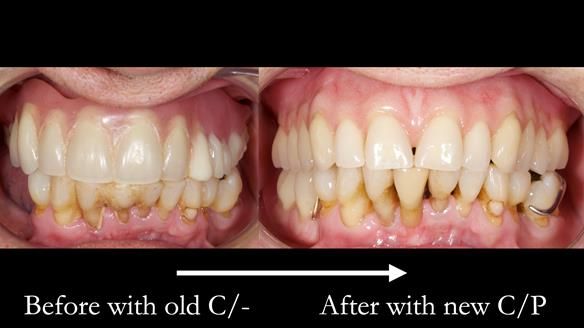

Welcome to my Newsletter 54 showing the making and fitting of dentures (a complete upper metal reinforced denture, a lower immediate partial denture and a definitive Scandinavian designed, metal based lower partial denture) for David, a 75 -year-old man. The full protocol workflow is presented including the use of dentate photographs to mimic his natural teeth.

- Current complete upper denture had many technical problems. Poor retention, support, stability and tissue fit.

- Missing teeth on the lower right side. This makes the upper denture tip when chewing and biting.

Interestingly we found that the upper complete denture when finished and fitted didn’t have good enough retention for David’s satisfaction. It was relined by adding compound to the buccal flanges – to almost overextend into the sulcus to ‘create’ a sulcus, followed by using a light bodied silicone impression material. This improved the function of the C/-considerably. A lower Scandinavian hygienically designed lower RPD was also provided which helped with occlusal stability and reseating the upper denture – further improving the fit.